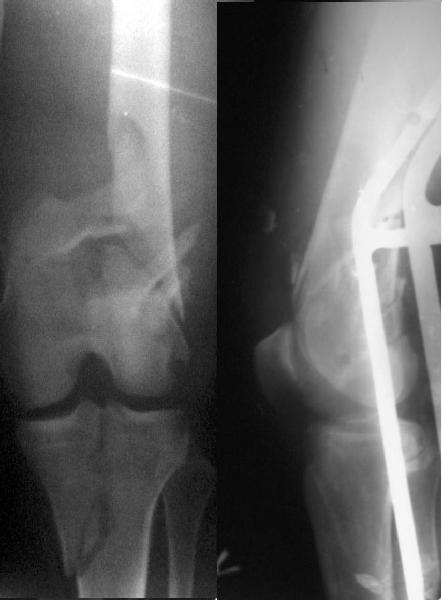

I would not say that the LISS is superior to the nail. If I would, I had not post original mail. I wanted to generate discussion. Your option is a very viable one. I feel a little bit shaky the distal femur, but it is just gut feeling no science behind it. Any way nice fixation, congarts!